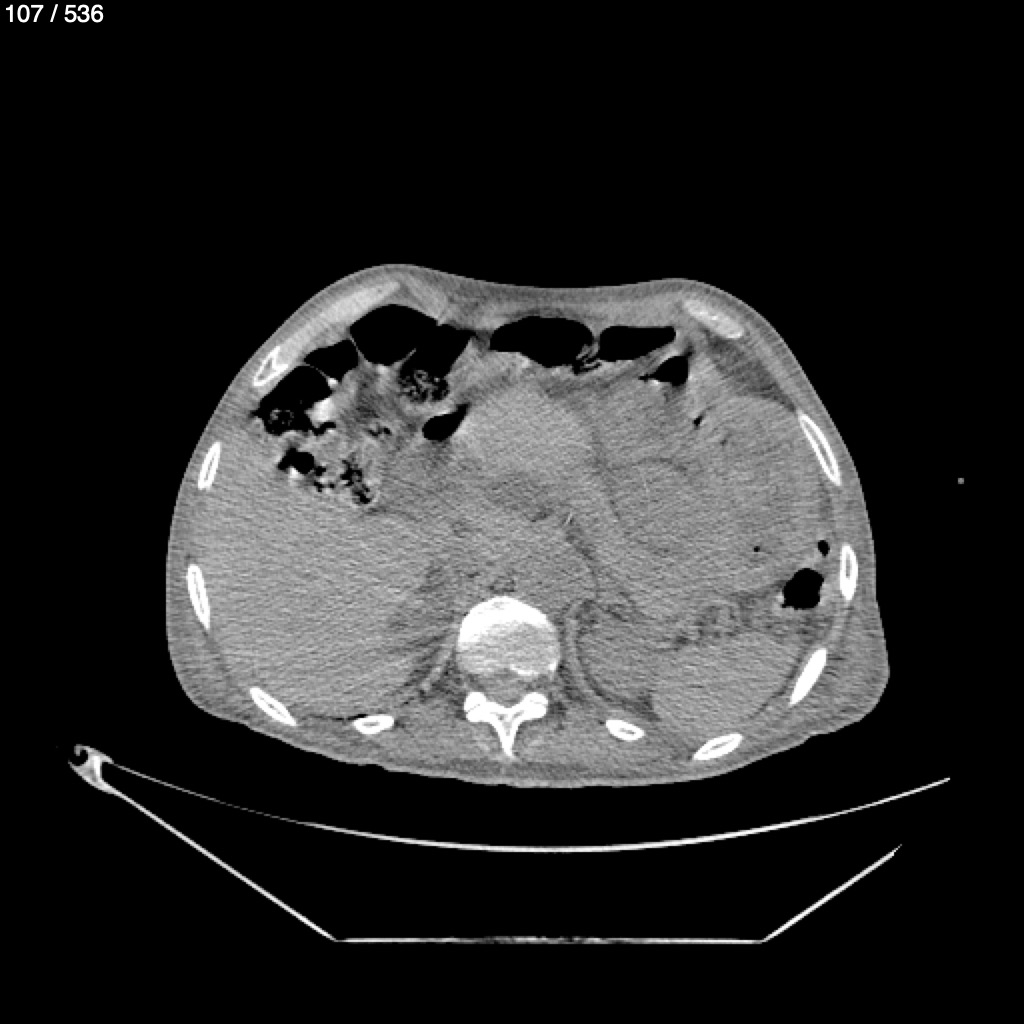

Angel Villalobos Palomeque 73 A - T.C Abdomen Simple